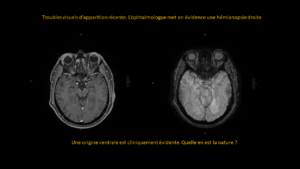

Deux mois après une entorse, persistance d’une importante douleur à la marche.

A droite pour comparaison, une radiographie de cheville qui est normale.

A gauche, le cheville du patient…quel est votre diagnostic?

RÉPONSE

Sur la radiographie simple, il est très difficile de visualiser la problématique.

La persistance de la douleur impose de réaliser une IRM qui révèle alors une fracture du calcanéum.